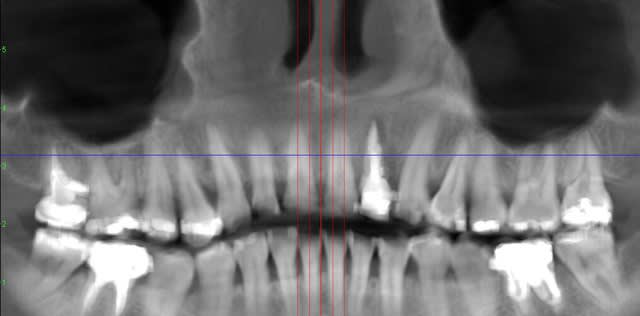

rhizalyse, tu as la chance ici d'avoir une occlusion en bout à bout et donc de pouvoir assurer la temporisation soit par une petite dent amovible ou collée aux voisines sans être absolument obligé de recourir à une extraction implantation et reconstitution immédiate. j'ai vu hier un patient où je n'aurai pas le choix car il est en classe II div 2 avec ses incisives inf qui sont en contact avec la muqueuse palatine et qu'il existe un diastème important entre le 22 et le 23. Dans ce cas je vais extraire, cureter, implanter en position palatine, positionner une membrane et combler grassement avec un mélange d'os autogène (du forage) et de matériau très peu résorbable d'origine animal ou synthétique.

Horiz b69fha - Eugenol

Coupes xo2gnm - Eugenol